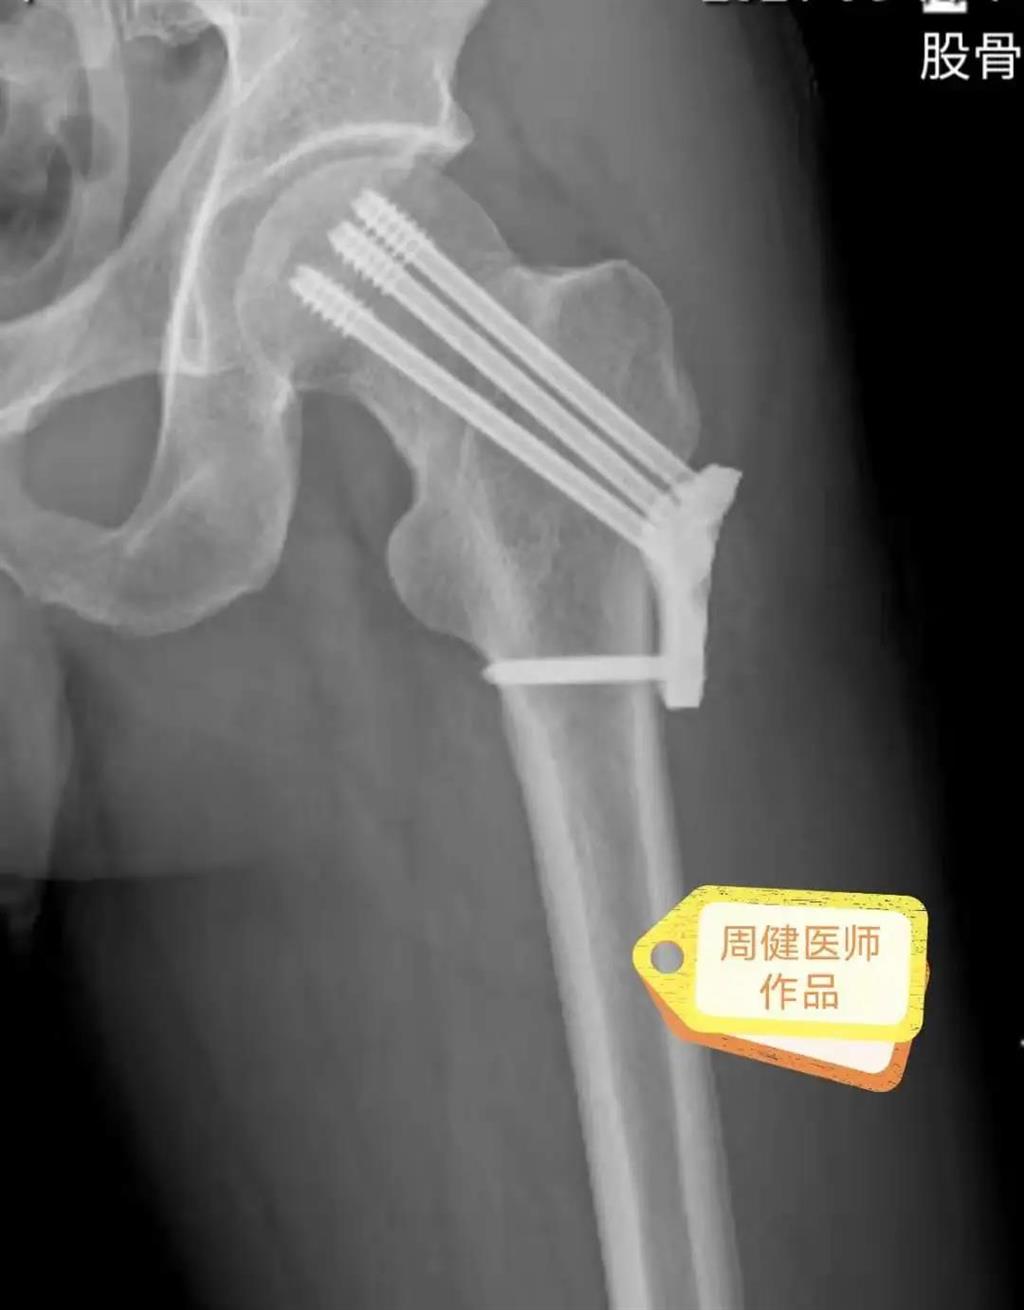

6月30日的“關(guān)節(jié)置換術(shù)”,患者是一位上了年紀(jì)的老人,苦于病痛折磨多年的他四處“求醫(yī)問藥”,最后在多位專家醫(yī)師及病友地力薦下選擇了和平國際醫(yī)院,在醫(yī)師團(tuán)隊“偷天換日”般的手術(shù)后,老人成功告別了苦纏多年的病痛。

周健說,這場“關(guān)節(jié)置換術(shù)”對于他們團(tuán)隊而言其實算是比較普通的手術(shù),因為做過很多同類的手術(shù),成功案例繁多,因此在手術(shù)操作上有較多地實操經(jīng)驗。“不過話雖如此,作為醫(yī)生我們對于每一場手術(shù)都會全力以赴,這是為醫(yī)者的職責(zé)也是義務(wù)。”